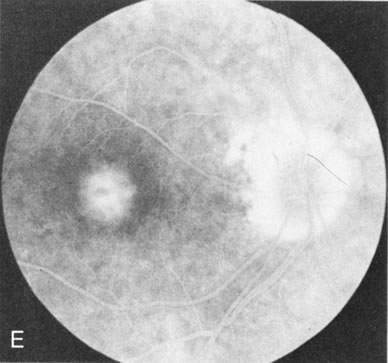

Of more clinical importance is the role of FA in the diagnosis and treatment of cystoid macular edema (CME) (Fig. 1C and D). Stereoscopic FA indicates that the leakage, which may be diffuse or have the typical petaloid stellate appearance of CME, can come from the perifoveal retinal capillaries, from the choroid through the RPE, or from a combination of both sources.4 With the recent suggestion that CME in RP may be successfully treated with acetazolamide,5, 6 FA is thus important to document the diagnosis of CME, establish the origin(s) of leakage, and follow patients during and after therapy.